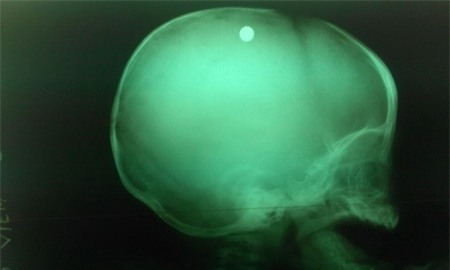

Viên đạn trong đầu bé trai 6 tuổi qua chụp X-quang- ảnh BV nhi đồng 2. |

Các bác sĩ đã nhanh chóng xác định đây là trường hợp bị thương ở sọ não do hỏa khí gây ra, và cần phẫu thuật gấp vì kết quả chụp X- quang cho thấy viên đạn vẫn còn nằm trong sọ của bé.

Theo bác sĩ Đặng Xuân Vinh, viên đạn nằm trong nhu mô não, cách xương sọ 2cm.